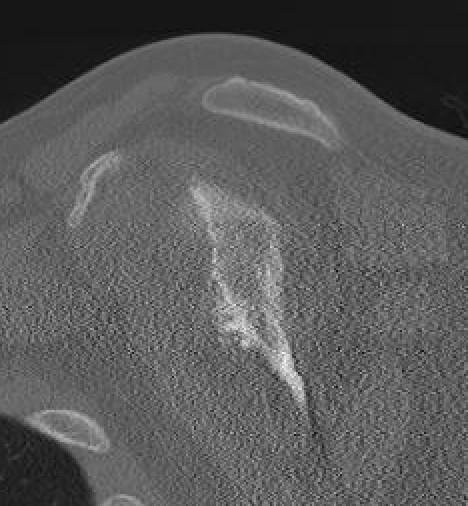

MRI

Rotator cuff tears

MRI with massive supraspinatus tear, subscapularis tear, and large Hill Sachs lesion